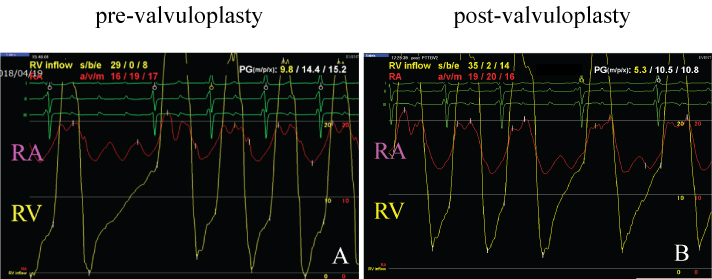

A 38-year-old male presented with right-side heart failure, with symptoms that included dyspnea on exertion, leg edema, and pleural effusion. Soon after birth, he had been diagnosed with incomplete atrioventricular septal defect. At two years of age, a surgical primum atrial septal defect closure, mitral valve plasty, and tricuspid valve plasty were performed. Because he developed severe tricuspid regurgitation at the age of five, a tricuspid valve replacement with a mechanical prosthetic valve (SJM27 mm) was performed. At the age of 20, stuck-valve and severe tricuspid stenosis occurred, and he underwent a second tricuspid valve replacement with a bioprosthetic valve (CEP27 mm). During surgery, an expansive pannus was observed. At the age of 29, the patient ceased medical follow-up. On admission, his physical examination revealed moderate edema in both legs. A Levine Grade III/VI, diastolic rumble also was auscultated at the lower left sternal border. A transthoracic echocardiogram revealed severely calcified, thickened, and immobile leaflets of the bioprosthetic tricuspid valve (Figure 1A, Movie 1). The peak velocity was 2.5 m/sec with a mean diastolic gradient across the tricuspid valve of 14 mmHg (Figure 1B). Tricuspid regurgitation was mild. An invasive hemodynamic study by cardiac catheterization revealed 9.8 mmHg of mean transvalvular pressure gradient and mean right atrial pressure that had elevated to 17 mmHg. The tricuspid valve area was measured as 1.0 cm2 by Gorlin's equation (Figure 2A). He also had two major comorbidities. The first was hepatic cirrhosis due to the hepatitis B virus and a congestive liver; the second was a progressive post-mediastinum tumor, the size of which was 50 × 55 mm. His fourth sternotomy was considered a high-risk procedure. His hepatic function also was thought to be insufficient for highly-invasive surgery. Therefore, the patient was offered a percutaneous transcatheter tricuspid balloon valvuloplasty, a less-invasive procedure.

Figure 2: A) Cardiac catheterization revealed 9.8 mmHg of mean transvalvular pressure gradient and mean right atrial pressure that had elevated to 17 mmHg. The tricuspid valve area was measured as 1.0 cm2 by Gorlin's equation; B) After the procedure, mean transvalvular pressure gradient decreased to 5.3 mmHg, mean right atrial pressure was then reduced to 15 mmHg and the tricuspid valve area increased to 1.3 cm2. View Figure 2

A 14-Fr long sheath was inserted via the right femoral vein and the guide wire passed through the bioprosthesis to the right pulmonary artery. A 26 mm Inoue balloon (Toray Medical Ltd., Japan) was inflated to a maximum of 26 mm, equivalent to 96% of the bioprosthetic valve (Figure 3A and Figure 3B). After the procedure, mean transvalvular pressure gradient decreased to 5.3 mmHg, mean right atrial pressure was then reduced to 15 mmHg and the tricuspid valve area increased to 1.3 cm2 (Figure 2B). The echocardiogram revealed that peak velocity had decreased to 1.7 m/sec, with a mean diastolic gradient of 7.5 mmHg (Figures 1C and Figure 1D, Movie 2). Deterioration of tricuspid regurgitation did not occur.